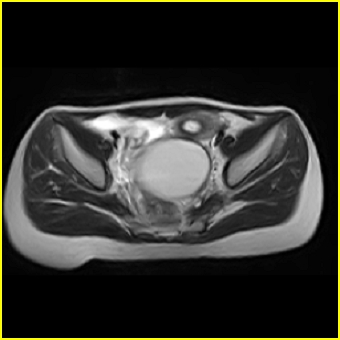

女、15岁、下腹疼痛2天,排尿困难1天。查体:处女膜闭锁,距处女膜约4至5cm处扪及一约5cm直径的圆形包块,张力较高,触痛明显、欠活动。b超提示子宫增大伴宫内增强回声团。

影像意见:子宫直肠陷凹积血。

更正影像意见:阴道积血。

处女膜闭锁,阴道积血

处女膜闭锁,阴道积血,子宫积血.

先天性处女膜闭锁,伴阴道积血,不除外先天性阴道粘液囊肿形成。

阴道积血,子宫积血.

子宫及阴道积血。

处女膜闭锁,伴子宫及阴道积血.